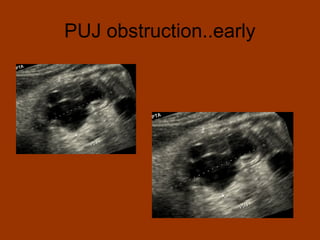

PUJ obstruction..early